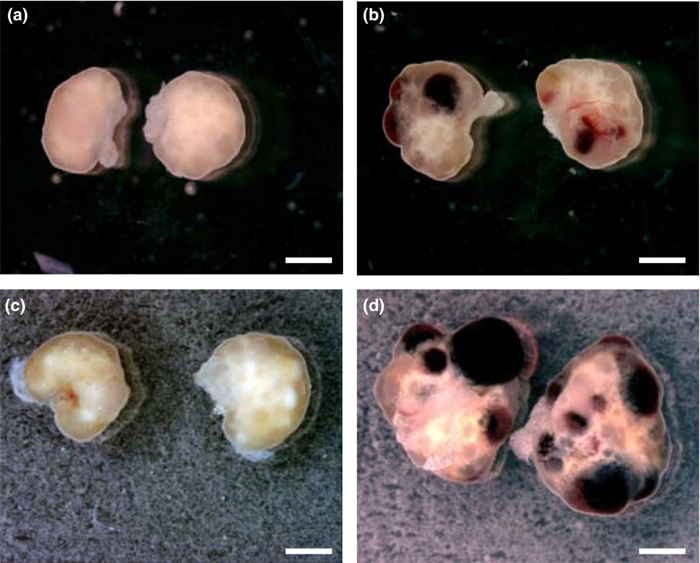

کیست های ساده (فولیکولی) با رشد قسمتی از تخمدان و تجمع مایع داخل آن مشخص میشوند، اندازه آنها معمولاً بالای ۳ سانتیمتر است و نباید با فولیکول تخمک که در زمان تخمکگذاری گاهی حتی به اندازه ۲۵ میلیمتر میرسد، اشتباه شوند.

نوع دیگری از کیست های تخمدان هستند که کسیت هموراژیک یا خونریزی دهنده نامیده می شوند. البته، این کیست ها بر خلاف اسمشان، معمولاً تأثیری بر باروری ندارند.

کیست های تخمدان کیسه ها یا کیسه های پر از مایع در داخل یا روی سطح تخمدان هستند. کیست های تخمدان خونریزی دهنده در طول تخمک گذاری زمانی که تخمک از طریق فولیکول تخمدان روی سطح آن آزاد می شود، ایجاد شده و آن فولیکول به داخل کیست خونریزی می کند. پزشکان نمی دانند چرا این اتفاق می افتد.